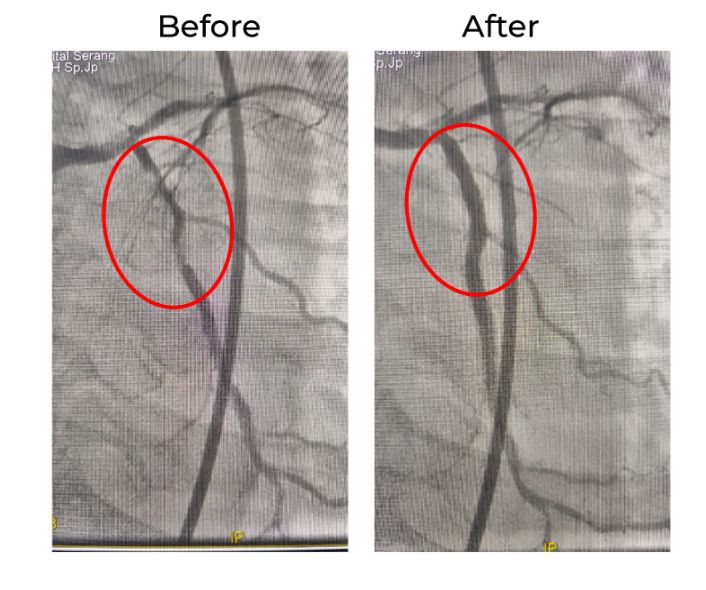

Prosedur rotablator untuk mengatasi penyumbatan pembuluh darah jantung

Di Bethsaida Hospital Serang, seorang pasien datang dengan keluhan nyeri dada yang mengarah pada gangguan aliran darah ke jantung. Saat dilakukan tindakan PCI, ditemukan lesi penyumbatan pembuluh darah jantung yang sangat sulit dilewati dengan teknik konvensional.

Upaya penanganan dengan PCI standar, Balloon Angioplasty, serta evaluasi menggunakan IVUS (Intravascular Ultrasound) telah dilakukan. Namun penyempitan pada pembuluh darah tersebut tetap tidak dapat dilalui sehingga aliran darah ke jantung belum dapat diperbaiki secara optimal.

Setelah melalui pertimbangan medis yang matang, pasien akhirnya ditangani dengan tindakan rotablator untuk mengatasi penyumbatan yang keras dan membuka jalan bagi prosedur intervensi selanjutnya.

Setelah prosedur rotablator dilakukan, pemasangan stent akhirnya dapat dilakukan di lokasi lesi yang sebelumnya tidak dapat dilewati.

Proses ini berjalan dengan lancar, memperbaiki aliran darah ke jantung dan mencegah terjadinya komplikasi lebih lanjut.

Evaluasi menggunakan IVUS setelah prosedur PCI menunjukkan hasil yang sangat baik. Ekspansi stent terlihat optimal dan aliran darah pada pembuluh yang dilakukan PCI mencapai TIMI 3, yang menunjukkan aliran darah lancar tanpa adanya penyempitan yang tersisa.